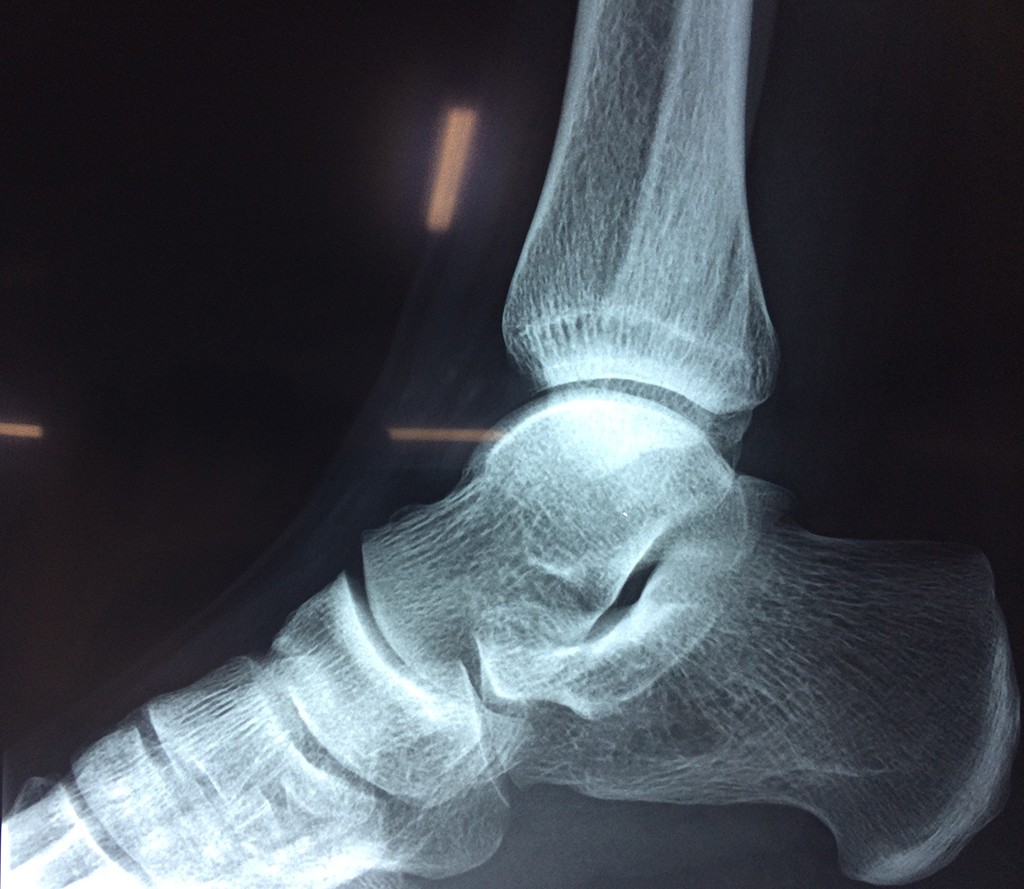

Una fractura de tobillo es la rotura de uno o más de los huesos del tobillo. Estas fracturas pueden ser:

- Parciales (el hueso está sólo parcialmente fisurado, no del todo).

- Completas (el hueso está perforado y está en 2 partes).

- Producirse en uno o ambos lados del tobillo.

Algunas fracturas de tobillo pueden requerir cirugía si: